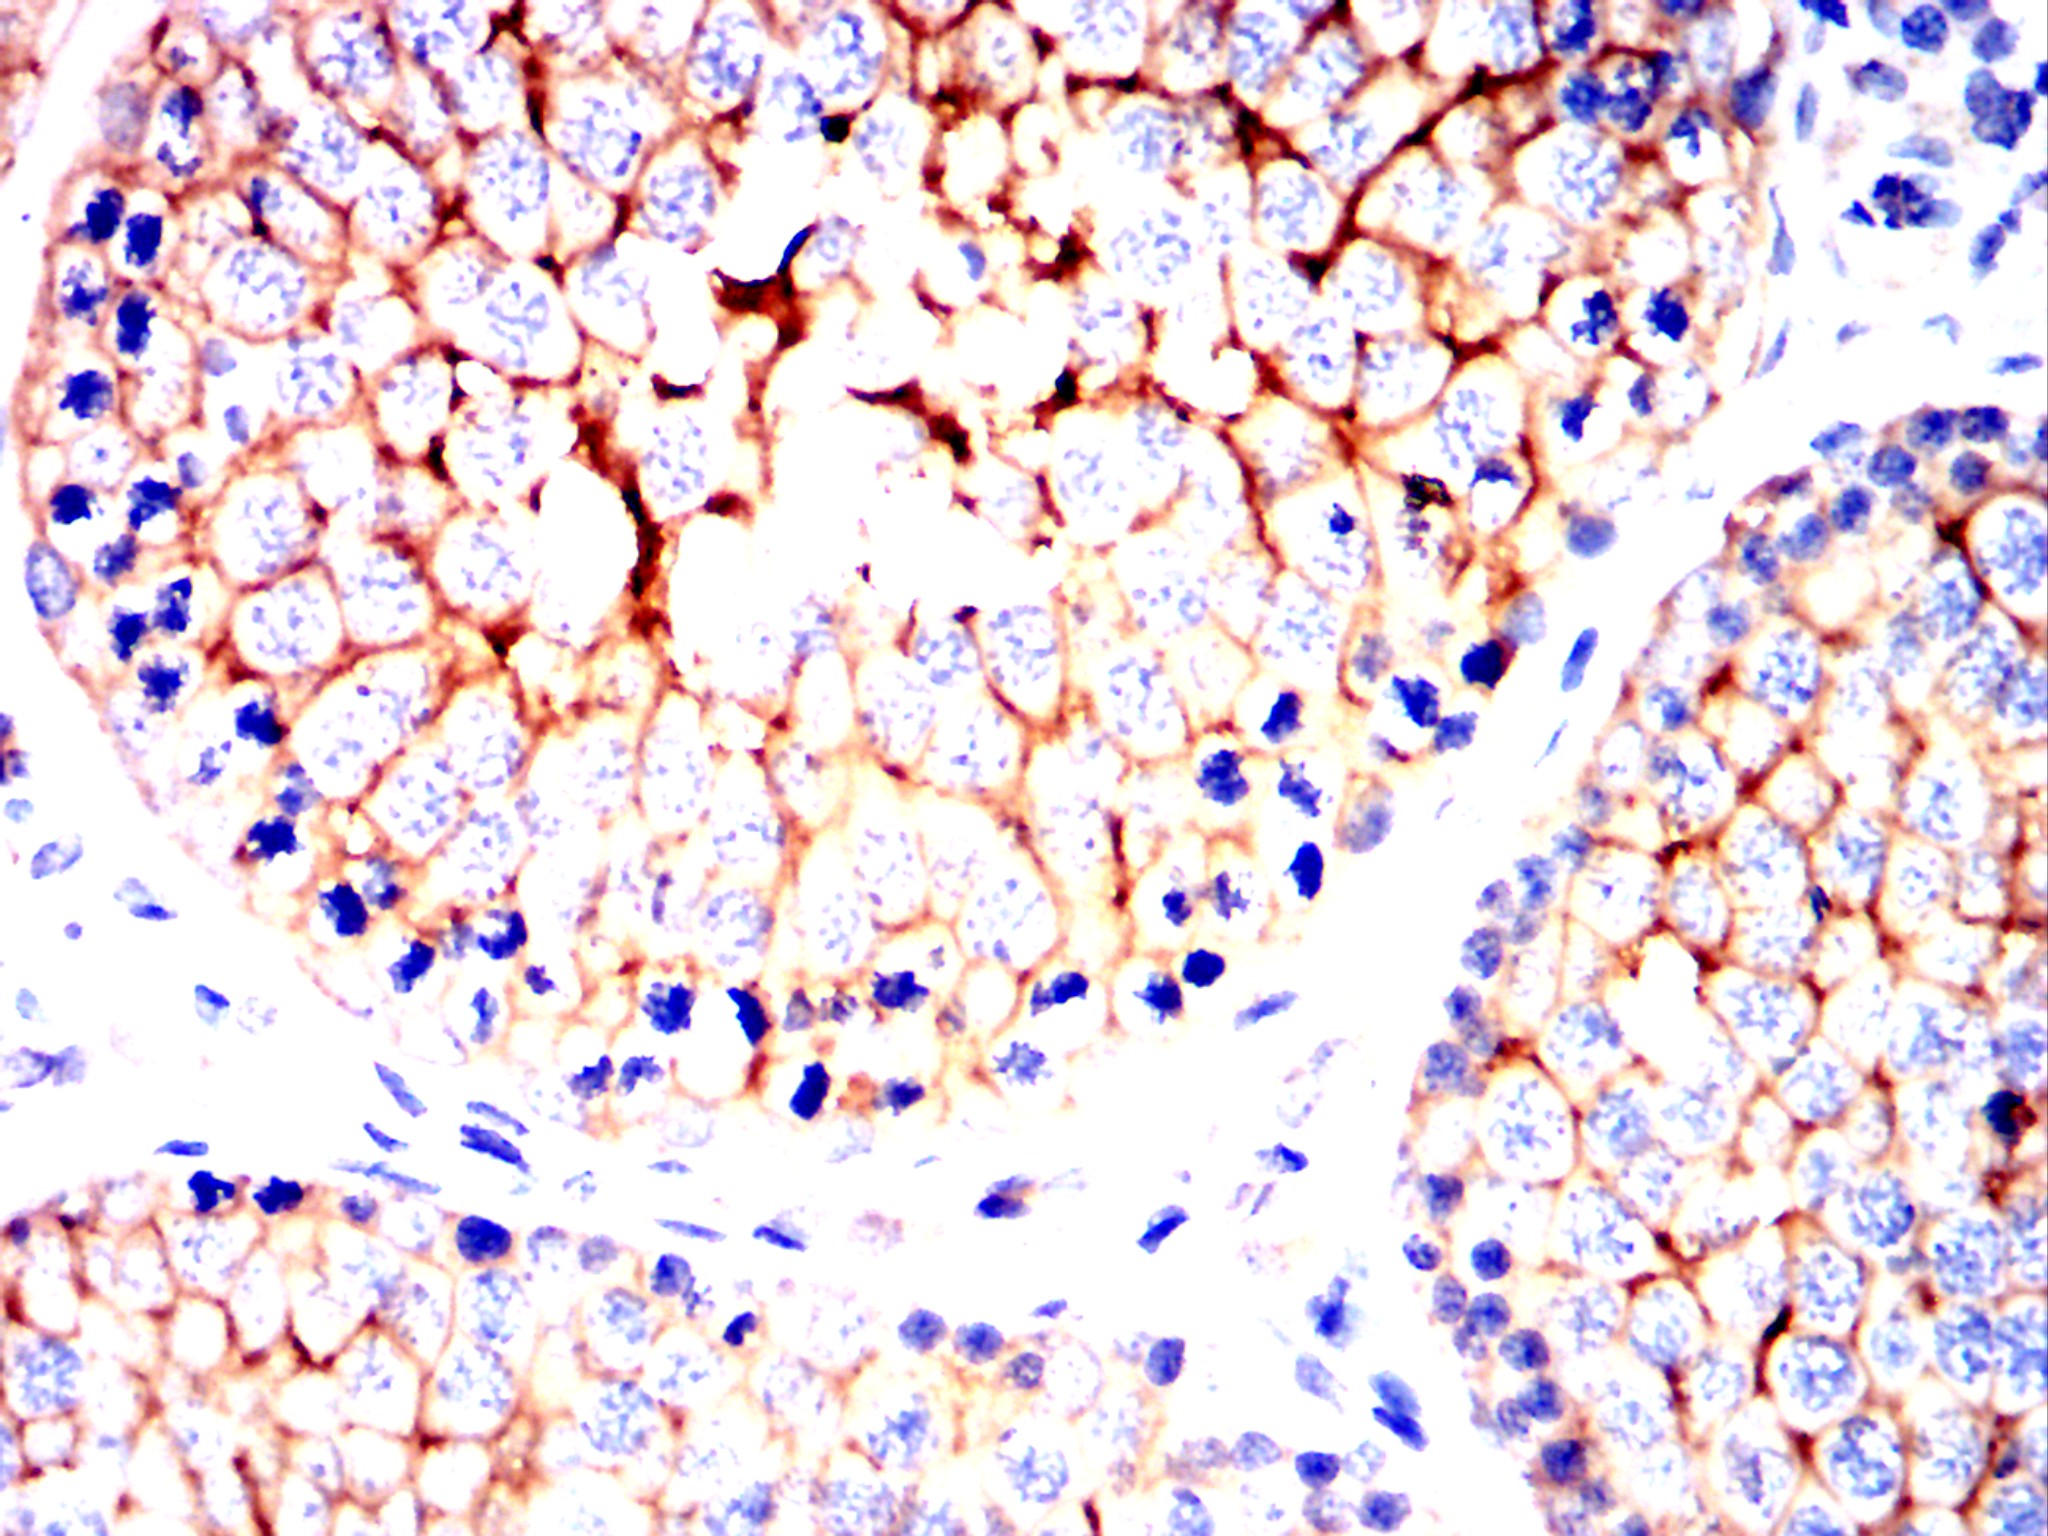

Immunohistochemical analysis of paraffin-embedded Mouse testis using NT5E mouse mAb with DAB staining.